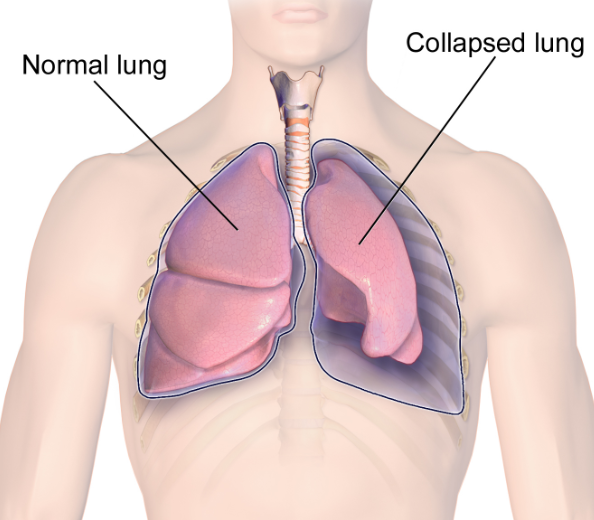

폐기흉은 폐를 싸고 있는 흉막 사이 공간인 흉막강 내에 공기가 새어 들어가 폐가 정상적으로 펼쳐지지 못하고 쪼그라드는 질환입니다.

이 질환은 발생 원인과 증상이 매우 다양하지만, 가장 큰 원인은 폐 표면에 형성된 작은 공기주머니인 기포(소기포)가 파열되어 흉막강으로 공기가 유입되면서 시작됩니다.

기흉이 심해지면 흉막강 내 공기가 계속 축적되어 폐와 심장을 압박하는 긴장성 기흉이 발생할 수 있는데, 이 상태는 생명을 위협하는 응급상황으로 혈압 저하, 청색증, 의식 저하 등이 나타나며 즉각적인 응급조치가 필요합니다. 진단 방법은 보통 흉부 X선 촬영으로, 허탈된 폐와 흉막강 내 공기를 확인하며, 더 정밀한 원인 분석과 확진을 위해 흉부 CT를 시행하기도 합니다. 청진 시에는 기흉이 있는 쪽 가슴에서 호흡음이 감소하거나 사라진 점도 진단에 도움이 됩니다.